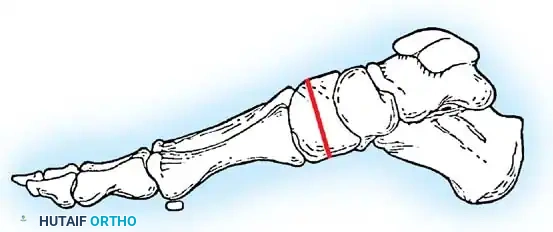

Hallux valgus (lateral deviation of the great toe) is not a single disorder, as the name implies, but a complex deformity of the fi rst ray that frequently is accompanied by deformity and symptoms in the lesser toes (Fig. 78-1). Often the angle between the fi rst and second metatarsals is more than the 8 to 9 degrees usually considered to be the upper limits of normal. The valgus angle of the fi rst metatarsophalangeal joint also is more than the 15 to 20 degrees considered to be the upper limits of normal (Fig. 78-2). If the valgus angle of the fi rst metatarsophalangeal joint exceeds 30 to 35 degrees, pronation of the great toe usually results. With this abnormal rotation, the abductor hallucis, which is normally plantar to the fl exion-extension axis of the fi rst metatarsophalangeal joint, moves further plantarward (Fig. 78-3). In this case, the only restraining medial structure is the medial capsular ligament with its capsulosesamoid portion (inserting into the base of the proximal phalanx) (Fig. 78-4) and capsulophalangeal portion (inserting into the plantar plate). The adductor hallucis, which is unopposed by the abductor hallucis, pulls the great toe further into valgus, stretching the medial capsular ligament (particularly the capsulosesamoid), attenuating this structure, and allowing the metatarsal head to drift medially from the sesamoids. In addition, the fl exor hallucis brevis, fl exor hallucis longus, adductor hallucis, and extensor hallucis longus increase the valgus moment at the metatarsophalangeal joint, further deforming the fi rst ray. The deep transverse intermetatarsal ligament runs between the plantar plates at the metatarsophalangeal joints and does not insert into bone on the adjacent sides of the metatarsal heads. Finally, the sesamoid ridge on the plantar surface of the fi rst metatarsal head (the crista) fl attens because of pressure (abutment) from the tibial sesamoid (Fig. 78-5). With this restraint lost, the fi bular sesamoid displaces partially or completely into the fi rst intermetatarsal space (see Fig. 78-2). In this situation, the patient is bearing less weight on the fi rst ray and more on the lesser metatarsal heads, increasing the likelihood of transfer metatarsalgia, callosities, and stress fracture of a lesser metatarsal.

Fig. 78-1 Multiple components of hallux valgus and associated deformities.